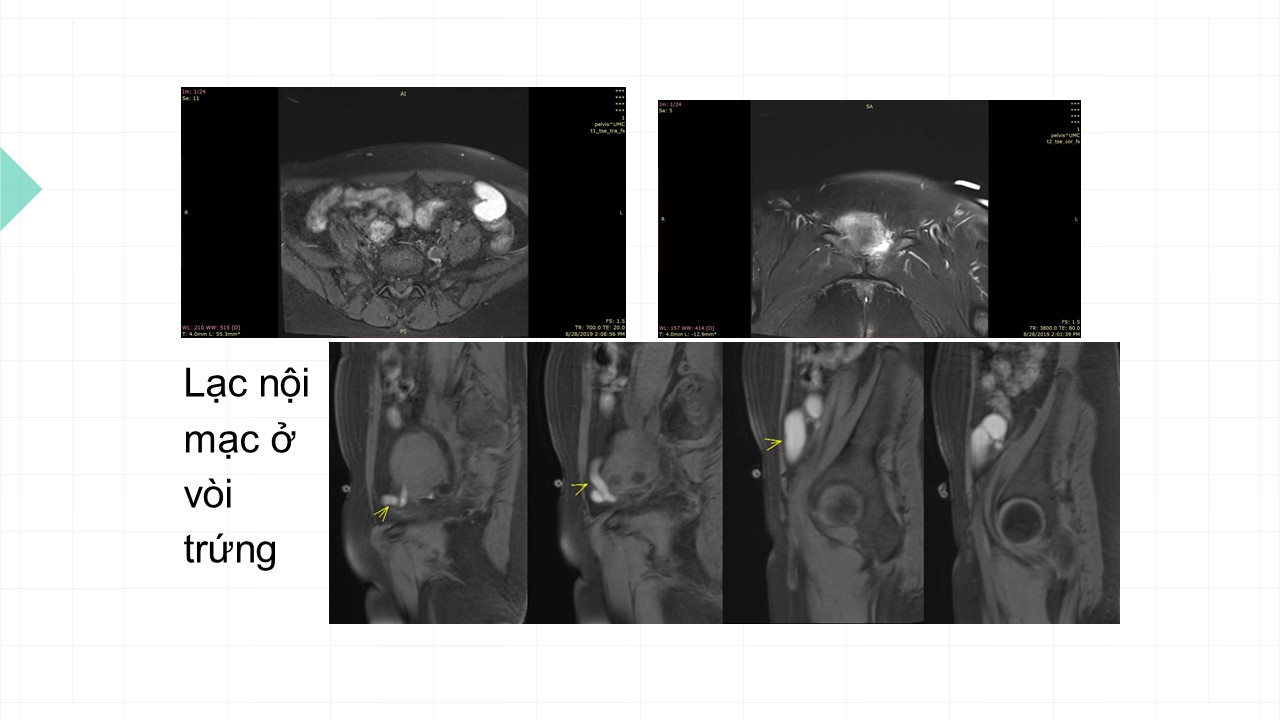

Vai trò cộng hưởng từ trong đánh giá lạc nội mạc tử cung

Từ khóa: Vai trò cộng hưởng từ trong đánh giá lạc nội mạc tử cung